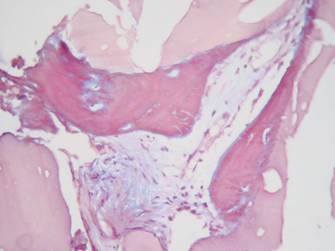

Resultados histológicos: Se procesaron un total de 11 muestras, todas las cuales fueron procesadas y coloreadas con hematoxilina y eosina, tricrómico de Masson y von Kossa para diferenciar el osteoide del hueso mineralizado

Tanto en las muestras del grupo 1 como del grupo 2 se encontraron cantidades moderadas de material amorfo eosinófilo (Grupo 1: 83,3%, Grupo 2: 80%), hueso propio maduro vital (Grupo 1: 83,3%, Grupo 2: 80%), tejido de granulación (Grupo 1: 66,6%, Grupo 2: 60%), vasos sanguíneos (Grupo 1: 50%, Grupo 2: 40%), osteoblastos (Grupo 1: 16,6%, Grupo 2: 20%) y osteoide (Grupo 1: 33,3%, Grupo 2: 20%). (Figuras 9, 10 y 11)

Con relación a los resultados histológicos de nuestro estudio, estos son similares a los reportados en investigaciones previas con injertos autólogos. Algunos autores reportan la generación de hueso laminar y trabecular en cantidades moderadas, con poca cantidad de vasos sanguíneos y cantidades variables de tejido de granulación (Figura 9).11,29,37,38 En las muestras procesadas con el tricrómico de Masson y von Kossa se encontraron resultados similares en ambos grupos, lo cual indica que tanto en el grupo 1 como en el 2 hay neoformación ósea (Figuras 10 y 11).